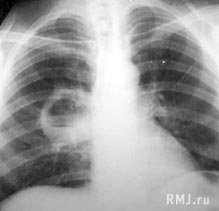

При рентгенографическом исследовании до прорыва абсцесса выявляется участок равномерного затемнения с округлыми контурами и увеличение лимфатических узлов у корня легкого. После прорыва гнойника в бронх определяется овальной формы полость с четкими границами (рис.5), горизонтальным уровнем жидкости и газовым пузырем над ней.

Рис. 5. Абсцесс правого легкого